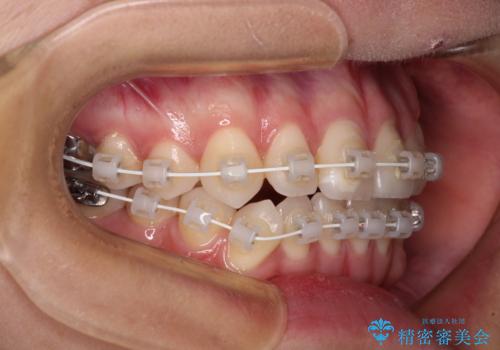

装置はワイヤー装置でもインビザラインのマウスピースでもどちらでも適用でしたが、自己管理の煩わしさを嫌い、ワイヤー矯正にて治療を行うこととしました。

ワイヤー矯正を選択されたため、鋏状咬合を確実に改善するために補助装置を併用することとしました。

ワイヤー装置でもマウスピースでも、どちらでも適用の症例でしたが、片側の鋏状咬合はマウスピース矯正ではしっかりと改善できる可能性が低いことや、何と言っても自己管理の煩わしさがないことから、ワイヤー装置を選択されました。